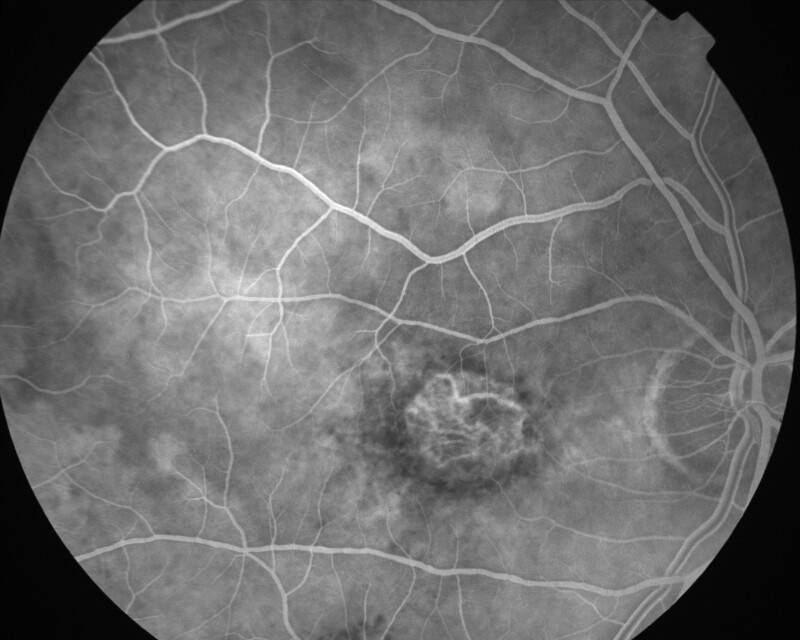

ATROPHIE AREOLAIRE CENTRALE